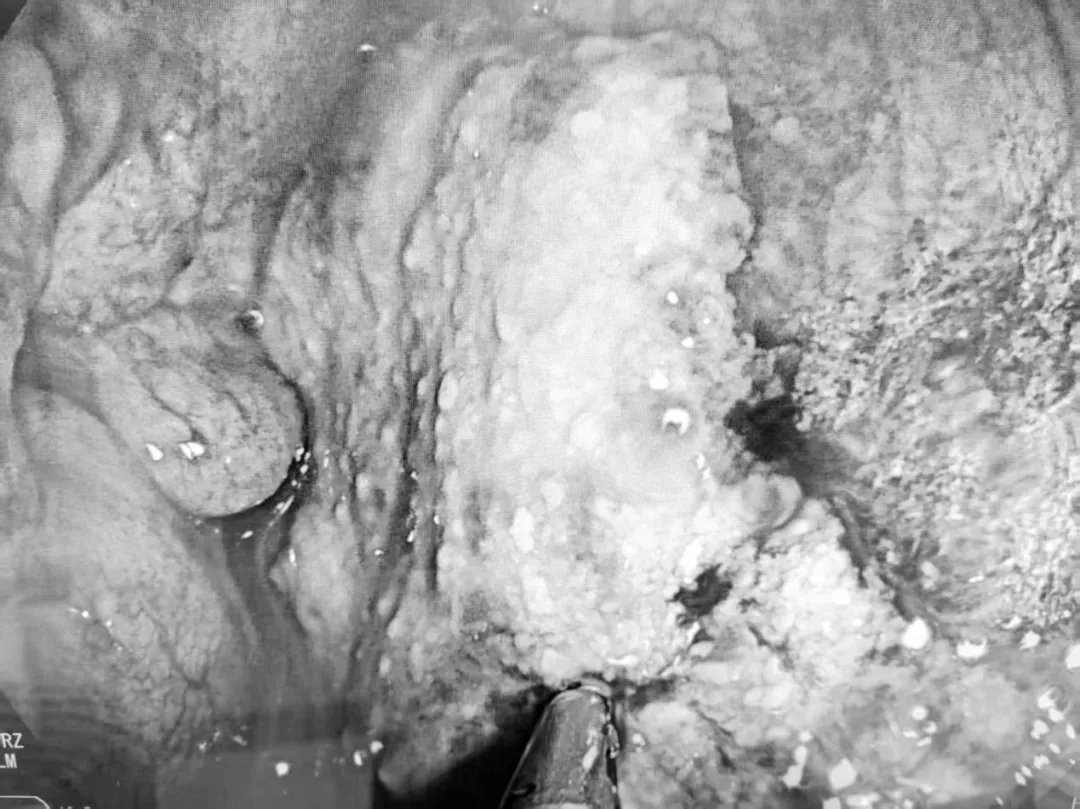

手术中,专家团队通过患者脐部这一天然褶皱处建立微小通道,将胃镜灵活引入腹腔。在清晰的內镜视野下,团队对腹腔进行了系统、全面的探查。最终,在腹腔内发现了腹膜病灶,并成功实施了精准活检。术后病理回报确诊为“高级别浆液性癌”。这一关键诊断,一举揭开了肿瘤来源的迷雾,为后续精准治疗指明方向。